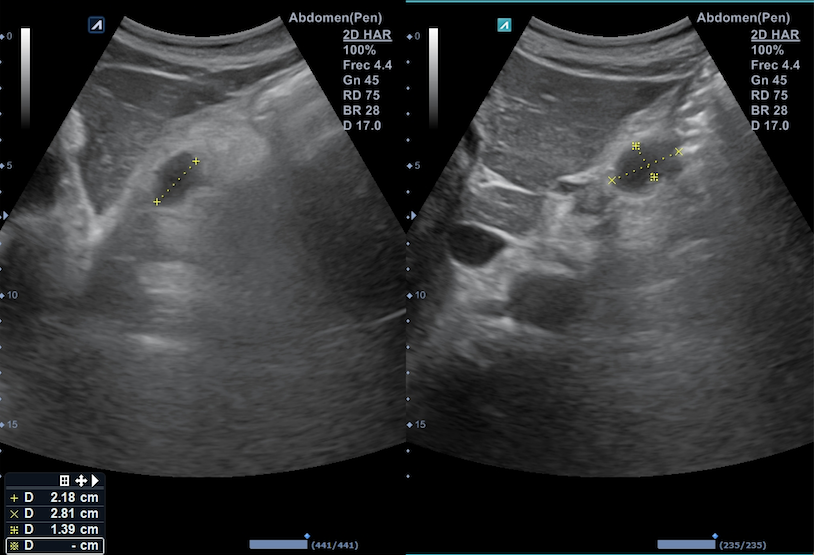

Citamos en consulta para realizar ecografía abdominal destacando a la exploración la presencia de 3 formaciones en retroperitoneo superior, en zona subdiafragmática y mediales al hiato aórtico: la primera a la derecha del tronco celiaco, de aspecto ovalado e isoecogénico de 1,2 x 1,9 cm; la segunda en línea media, debajo del lóbulo caudado, de aspecto hipoecogénico y con zona central de menor densidad de 1,9 x 2,2 cm; la tercera, a la izquierda de esta última de 2,2 x 2,8 cm sugerentes de adenopatías retroperitoneales.